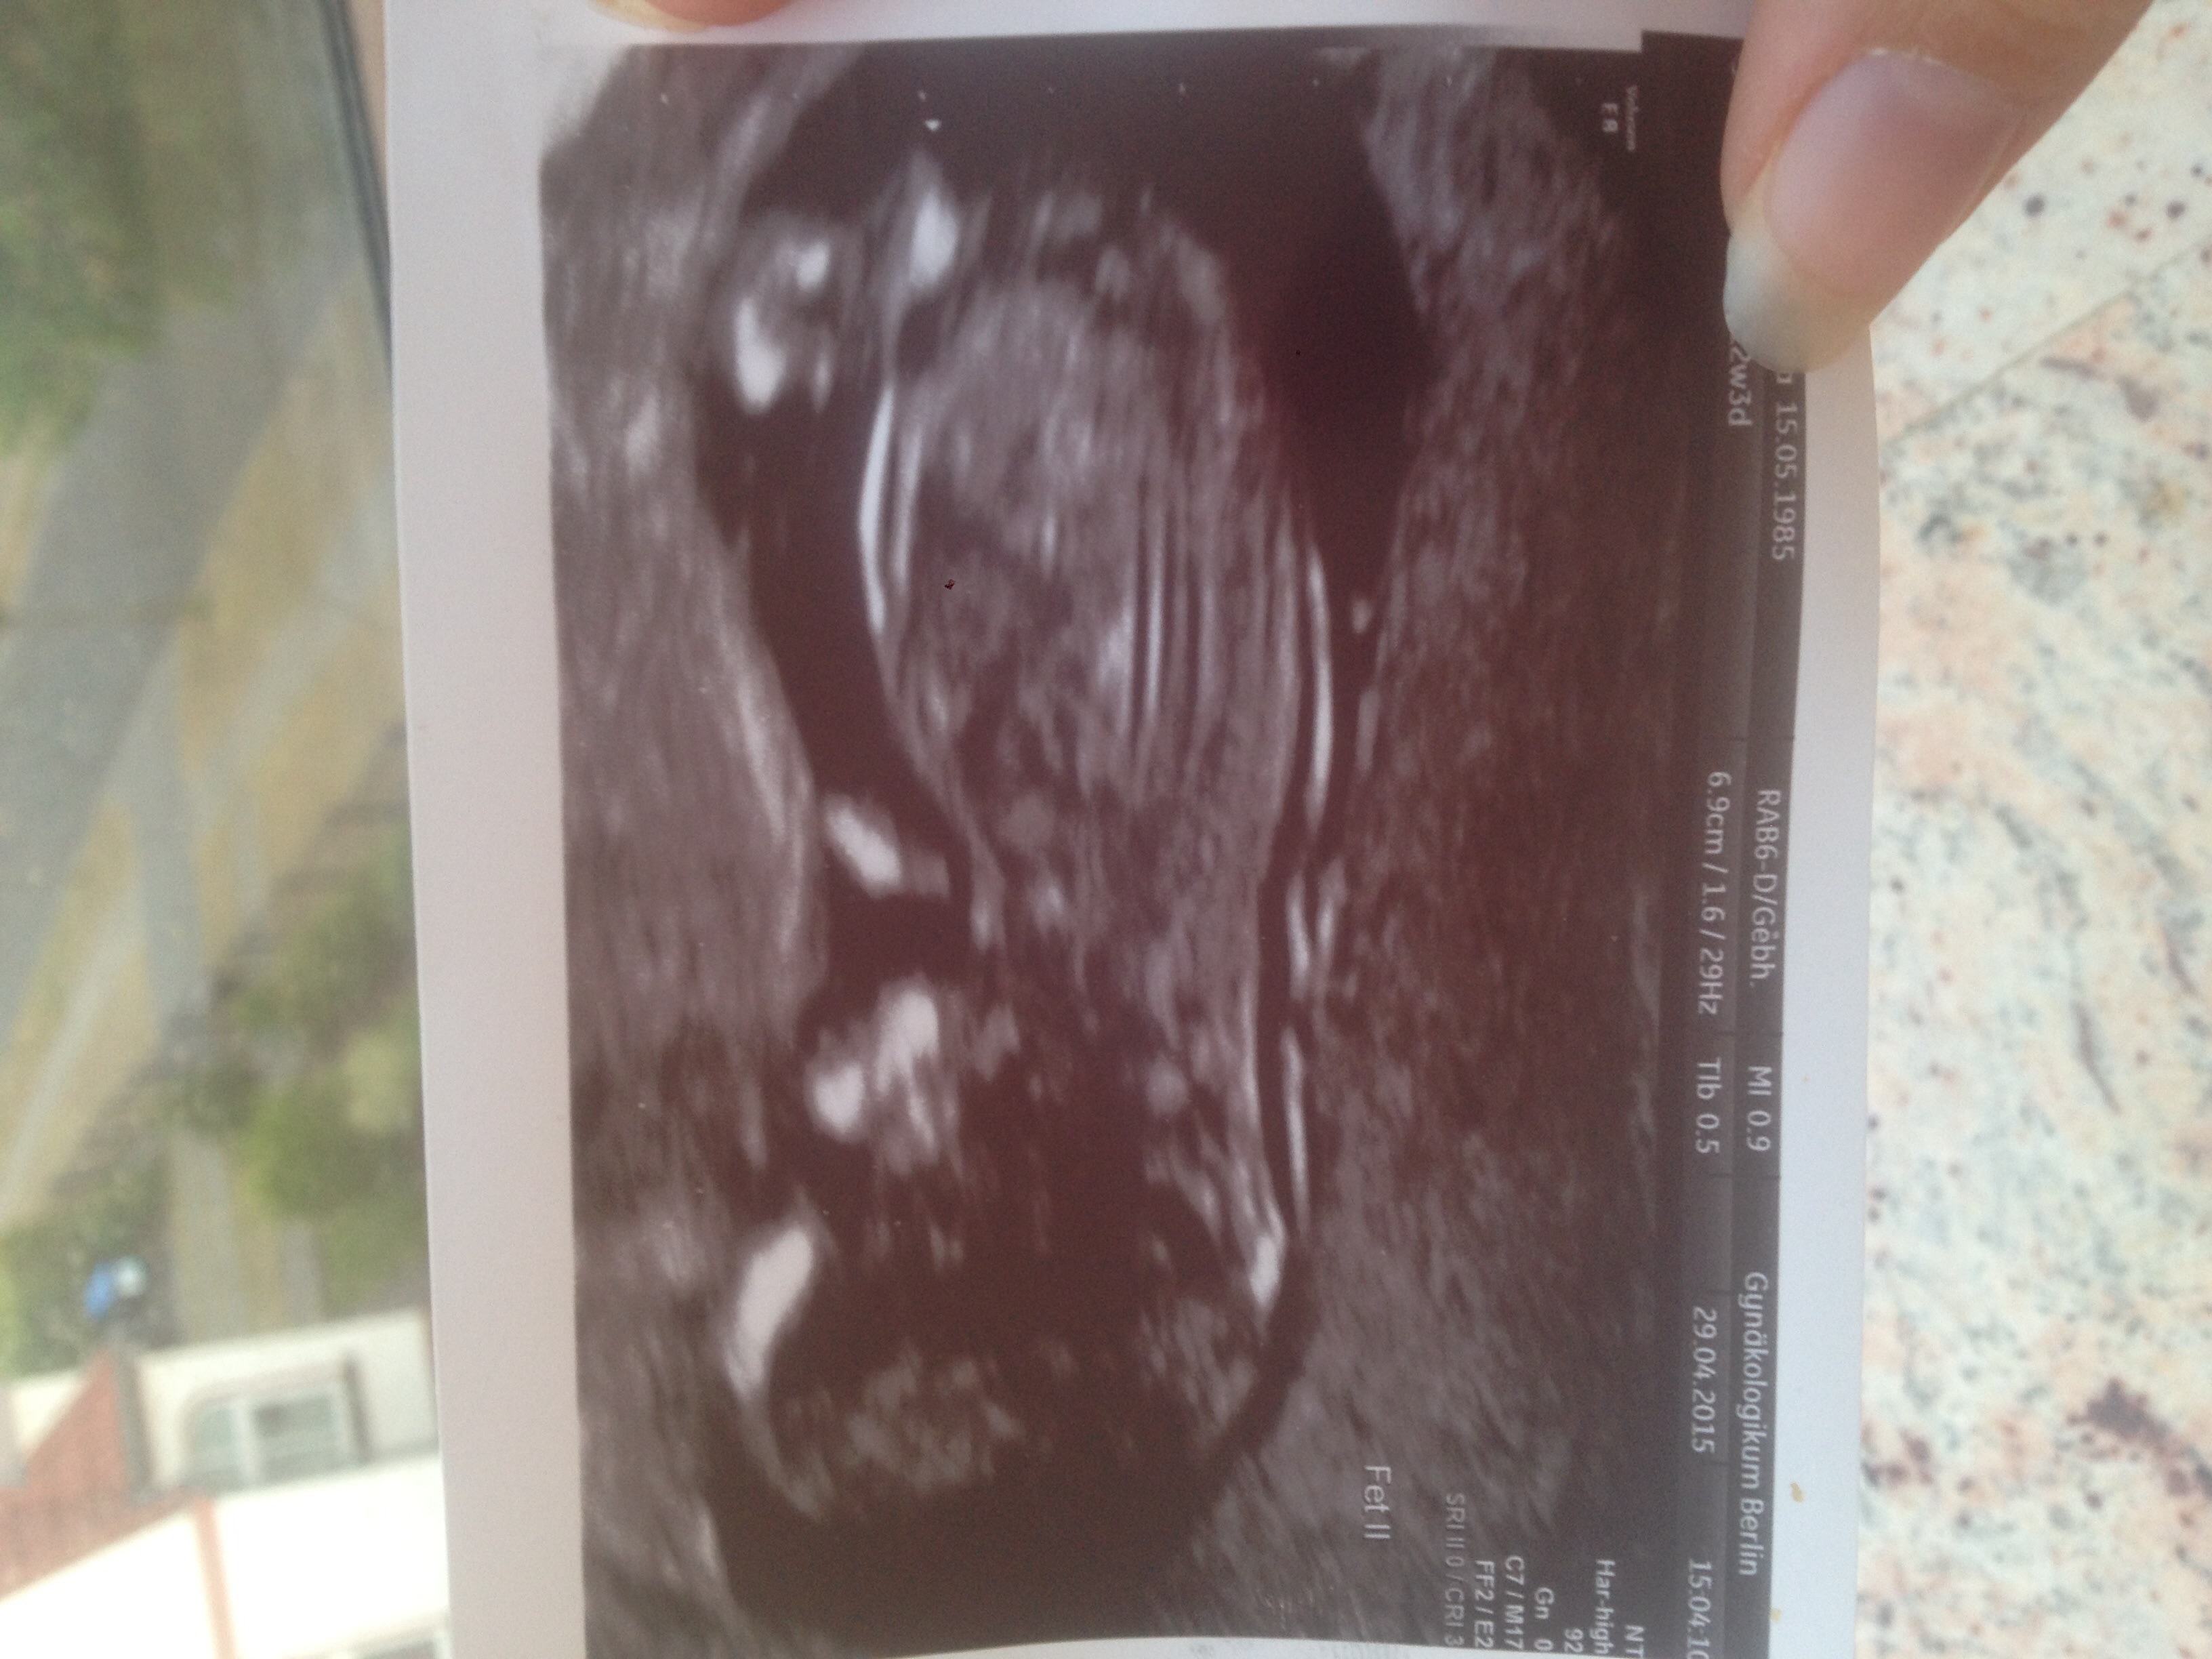

Hello. Is this really a Girly nub on the right side?

The tech said, it's a Babygirl -> 95% ;)

(Week 12+4)

No nub in this pic

Not seeing a nub but am getting a girly vibe from the head

yup sadly only like a smidge is captured of the nub but not enough. Hopefully the tech is right for you!